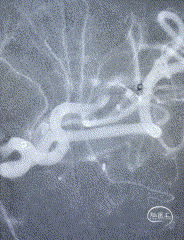

小血管血栓取栓病例

一例左侧大脑中动脉M3段闭塞远端

抽吸导管血管再通治疗

作者:高军、温昌明